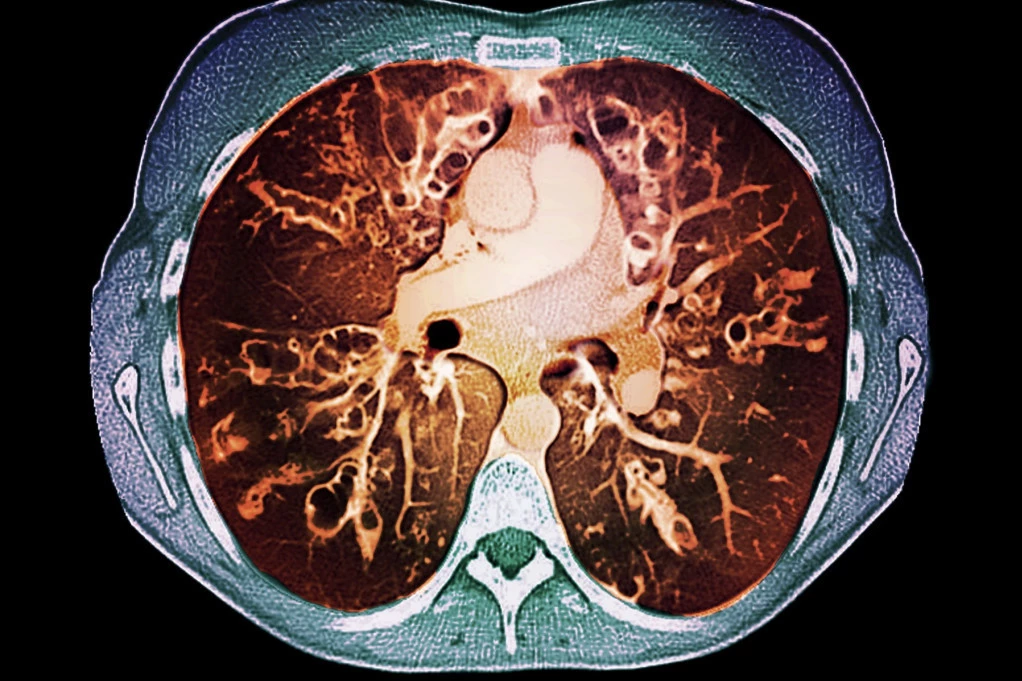

Cistična fibroza - Copyright Profimedia